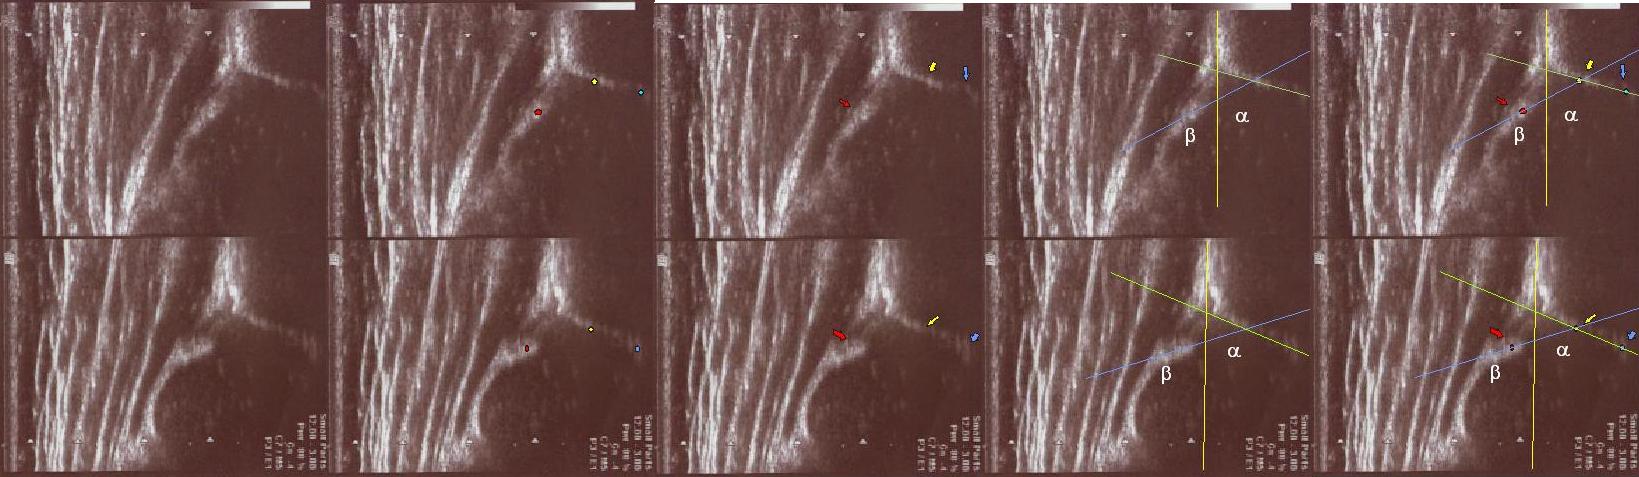

type II/D(up) 4 weeks the bony roof severely deficient ,

the bony rim flattened

the cartilage roof dispalced;

the arrows show labrum (red) ;

the bony rim (yellow);

the lower iliac margin (blue) ,

the bony roof line (green) is extends tangential to the lower iliac margin and tangential to the bony rim

the cartilage roof line(blue) is drown tangential to the bony rim and through the middle point of the labrum

the baseline (yellow) is drown parallel to ilium echo through the point of the junction of the perichondrium,the periosseum and ilium.

type IIc (up) 6 weeks the bony roof severely deficient ,

the cartilage roof still covers ;

the bone roof line (red)

the cartilage roof line(pink)

the baseline (yellow)

type D(up) 1 weeks the bony roof severely deficient ,

the bony roof line (green)

the cartilage roof line(blue)

type I (below) 6 weeks

asymmetry in the loose joint capsule;family DDH ( when it occurs ask always about it)

the bony roof is good

the bony rim blunt

the cartilage roof cover the head;

the bony roof line (blue) is extends tangential to the lower iliac margin and tangent to the bony rim

the cartilage roof line(green) is drown tangential to the bony rim and through the middle point of the labrum echo ;

asymmetry in the loose joint capsule ,family DDH( when it occurs ask always about it)

type Type GN (coming to maturity) (Physiologically immature, border type between I and II) (up ) 6 weeks

the bony roof is adequate